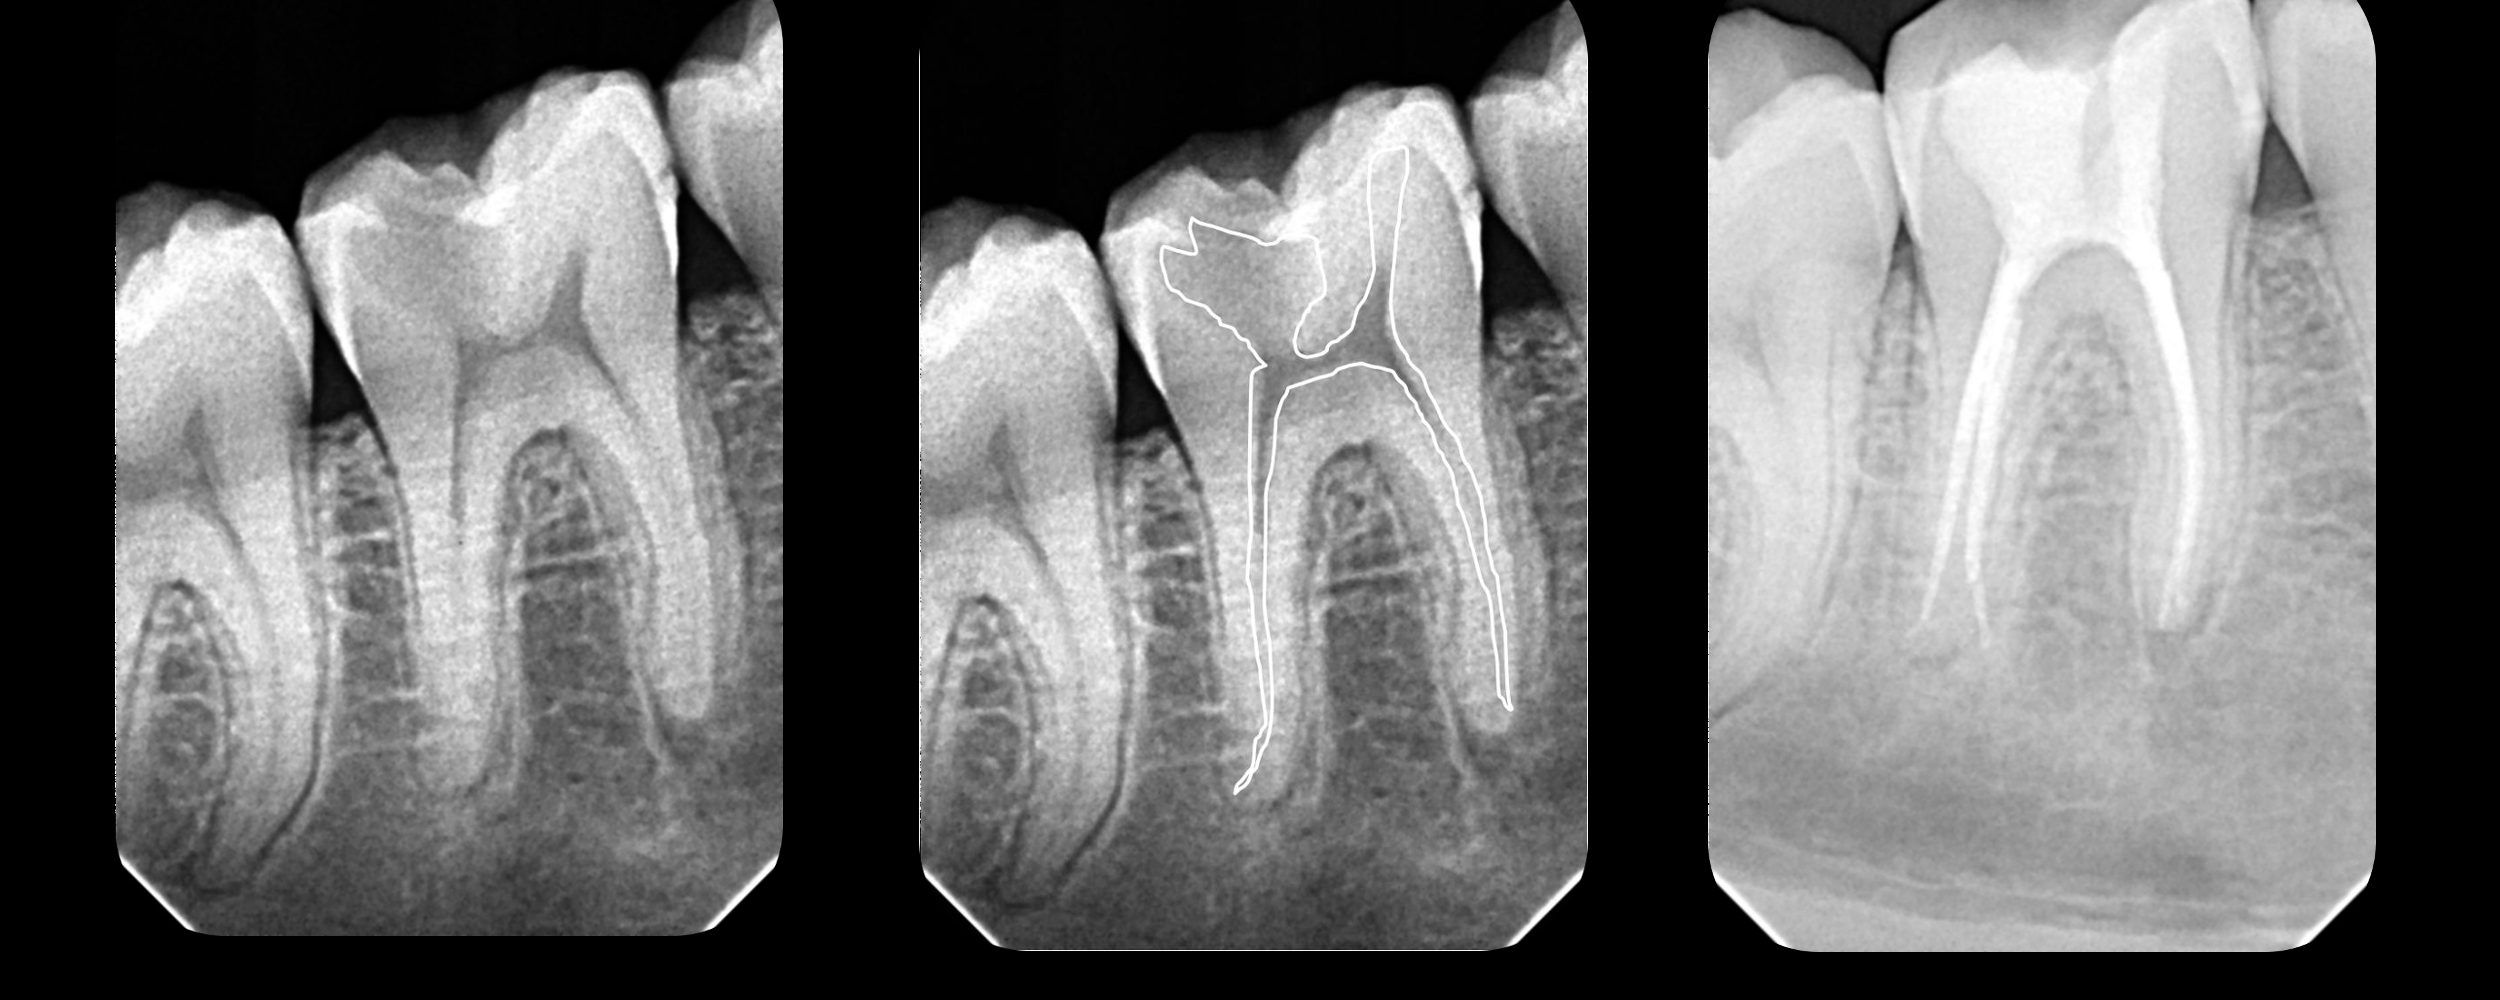

#30 RCT – 3 Distal anatomy – Truss access

#30 deep distal margin. Done in 2 visits. Gingivectomy and Pre-endo done. All canals shaped to 4% 25 obturated using WVC.